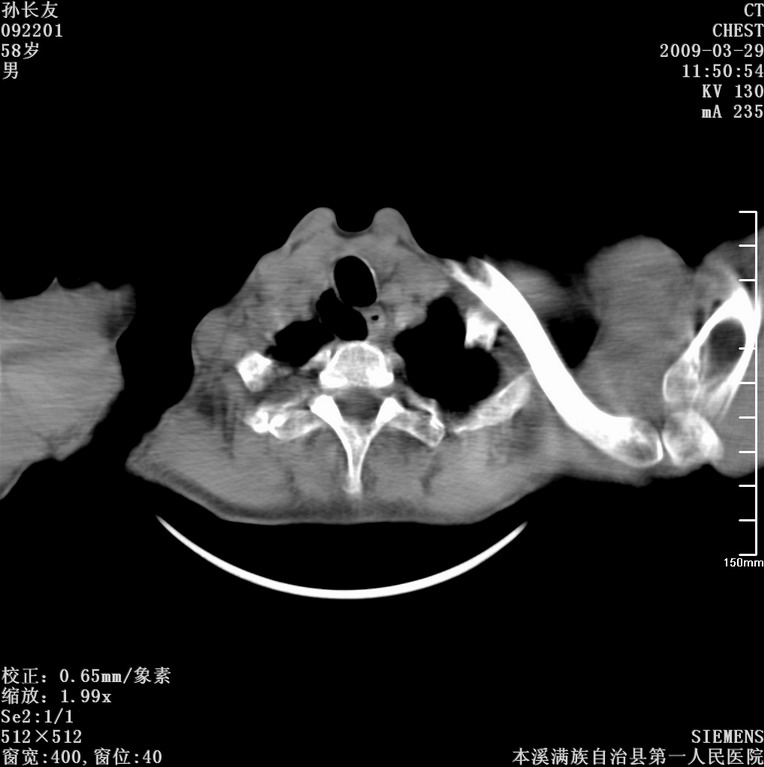

以下是引用bmw011在2009-3-30 12:09:00的发言:[br]所上传的层面示气管未见确切异常。